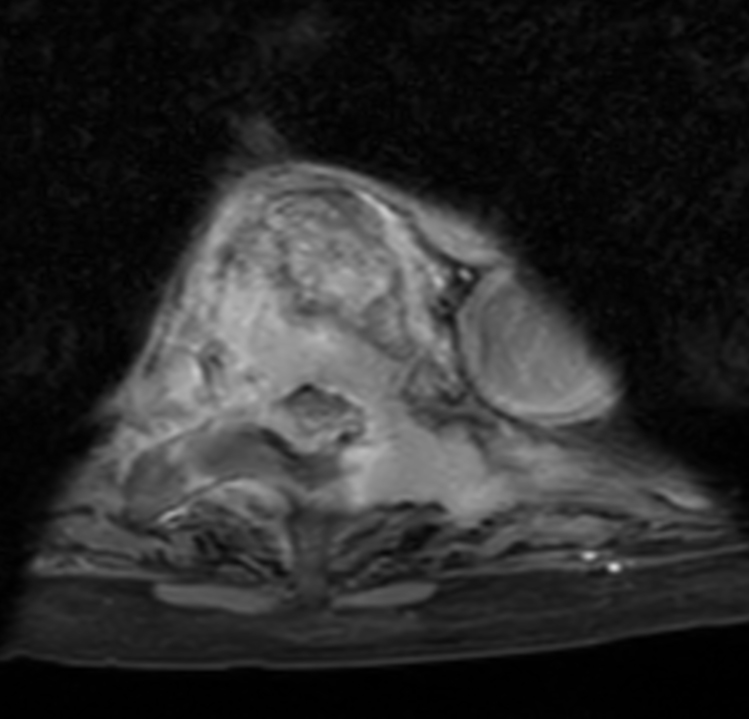

Axial T2w TSE - High res (T4)